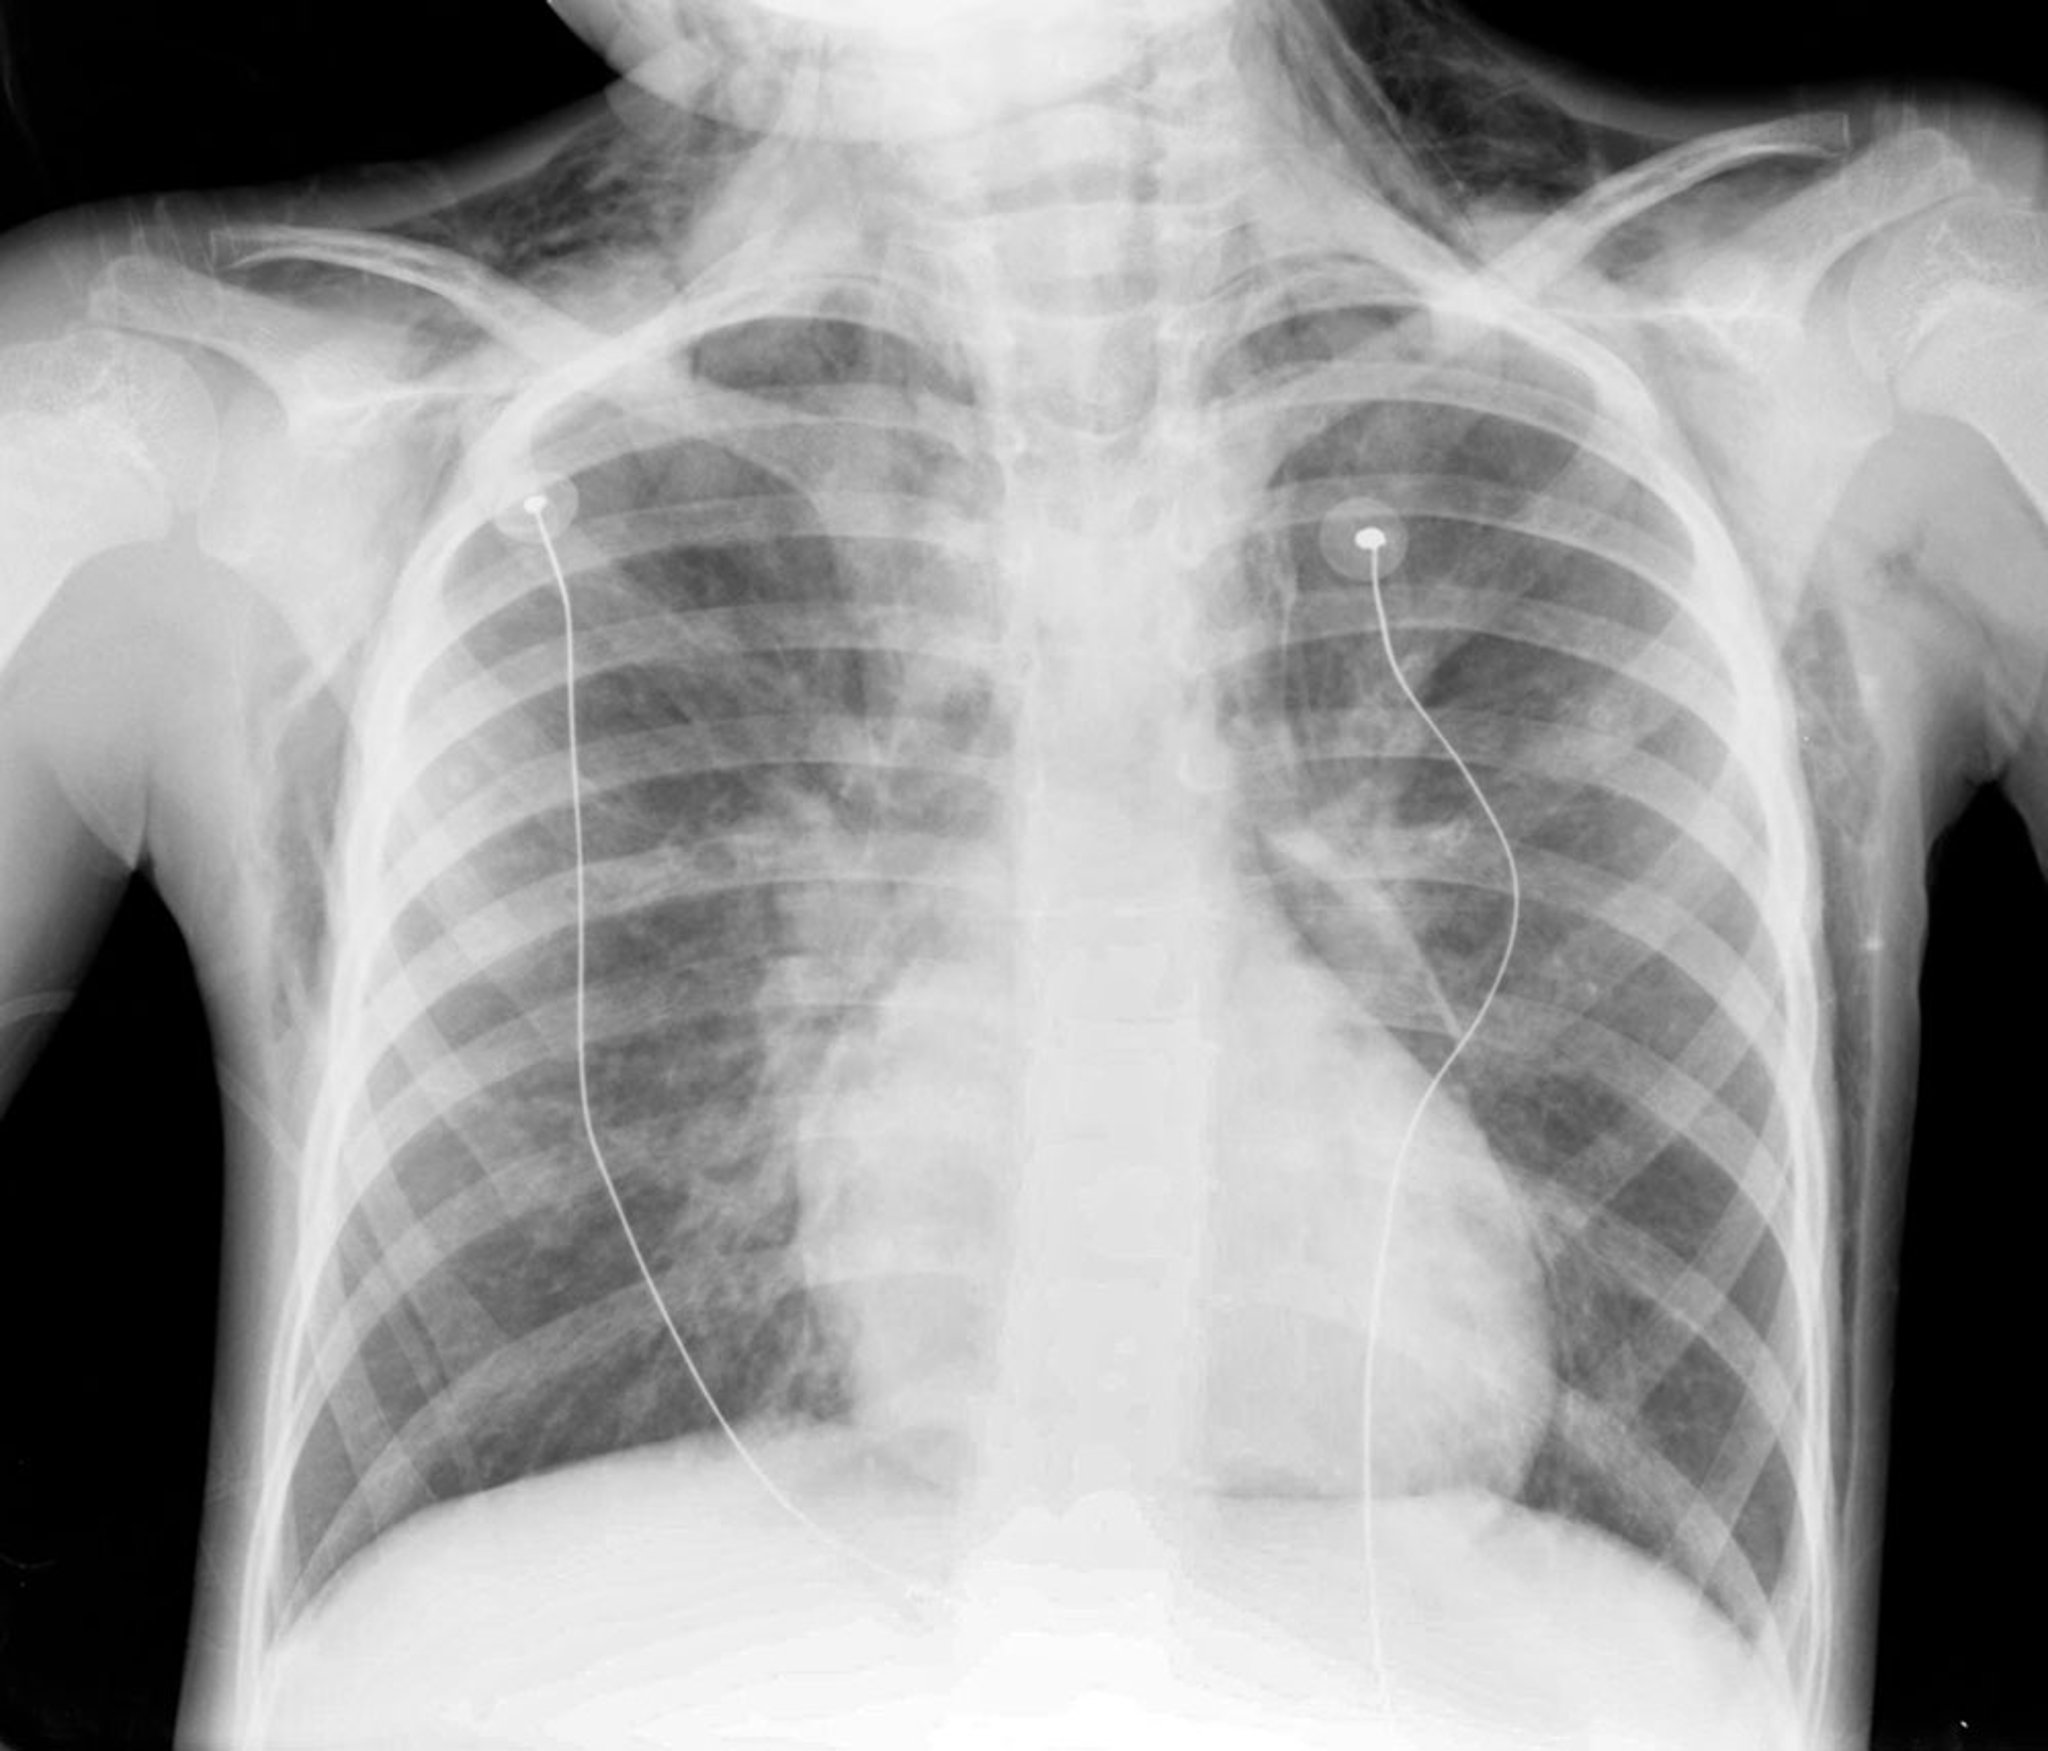

The diagnosis is confirmed by chest radiograph, which shows air in the mediastinum.